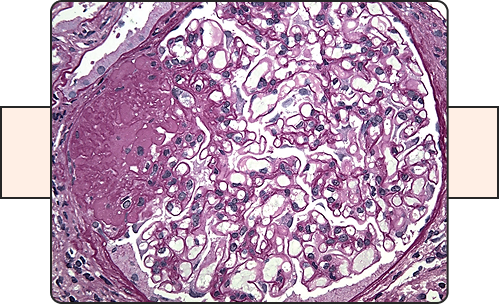

IgA Nephropathy

This Protocol will evaluate the efficacy of an investigational medication for adult patients with IGA Nephropathy, in addition to evidence based standard-of-care medications aiming at reducing the proteinuria with the goal is to delaying the progression of kidney disease.